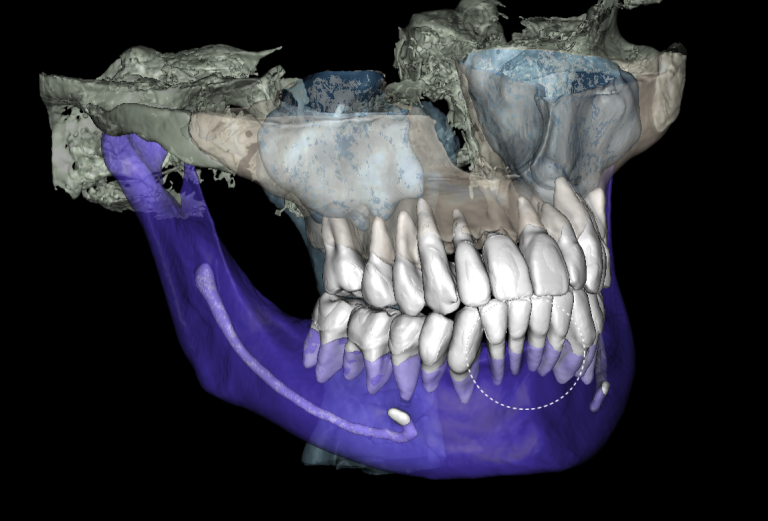

The “STL” module enables the creation of virtual models for guided implant surgery. This is achieved by loading intraoral scan data into the module and selecting a suitable CBCT for merging

The slide illustrates the sequence of stages involved in prosthetic rehabilitation, obtaining digital impressions and uploading them to the Diagnocat STL module, to creating temporary crowns and forming the desired emergence profiles for implants